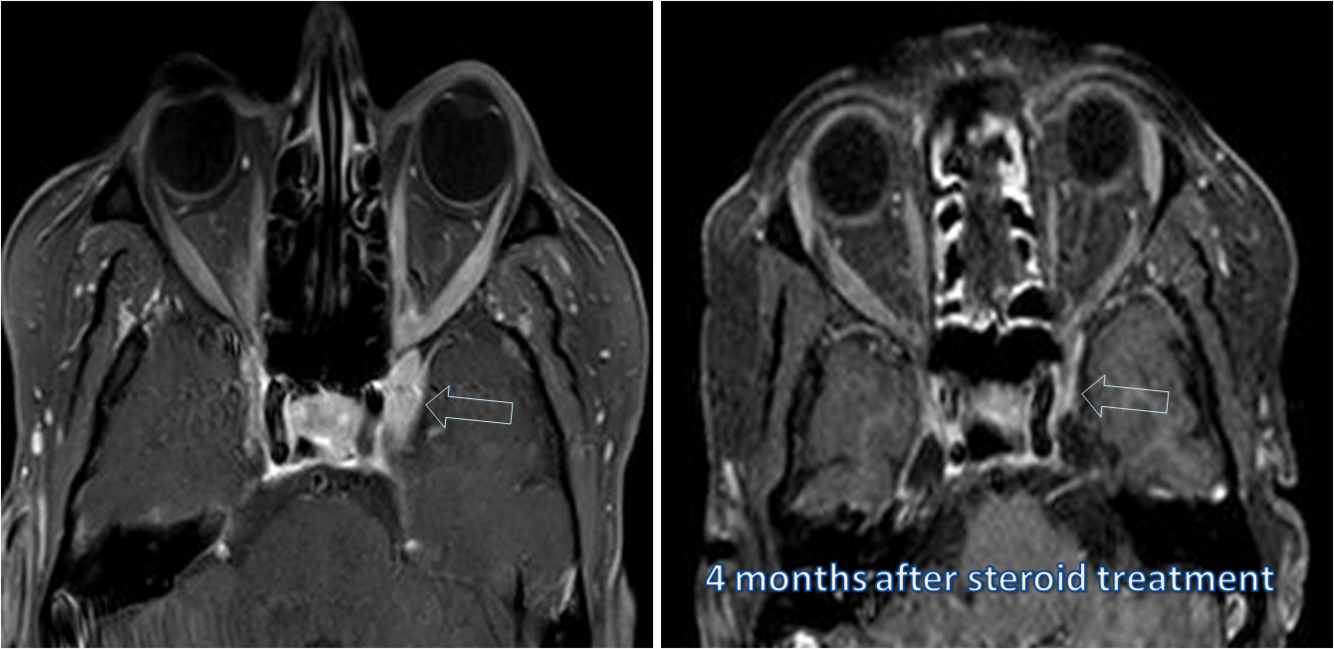

Treatment of Thyroid ophthalmopathy

Radiographic features of Thyroid Ophthalmopathy